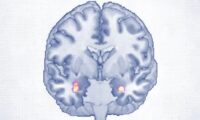

主任研究者のザカリア・クロス氏によると、この結果の違いはある特定の脳波と睡眠紡錘波に関連していると述べました。これらは、ノンレム睡眠中に同期する二つの脳波パターンです。

脳科学に絞った科学論文を集めた『ネイチャー・ニューロサイエンス』誌に掲載された総説によると、これらの脳波パターンは記憶の定着に関与していると考えられています。このパターンは、脳内の電気的活動を測定する脳波検査で検出できます。

「この記憶定着は、学習した情報が海馬から大脳皮質に伝達され、長期記憶の保存が促進されることを反映していると考えられます」とクロス氏はプレスリリースで述べています。

「睡眠後の神経活動は、認知制御と記憶の定着に関連する独特なシータ波のパターンを示し、睡眠によって誘発された脳波の協調が学習成果と強く関連していることを示唆しています」